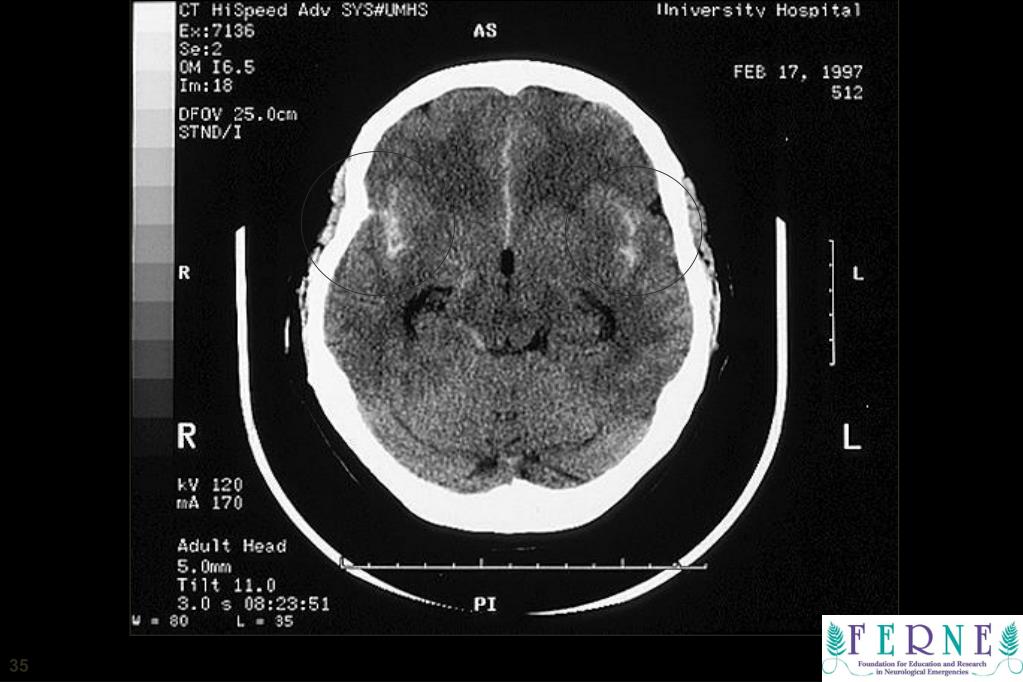

35. CT Scan 35

36. Intraventricular/Intraparenchymal Hemorrhage